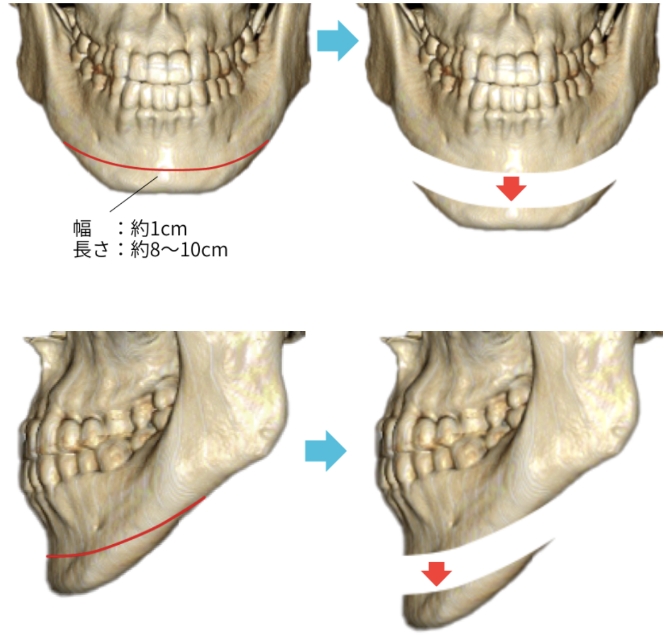

小木曽クリニックの

『下顎角形成骨切り術』の

特徴

骨切り量が非常に大きい

オトガイ神経を剥離して下顎骨を広範囲に露出し、神経の上下からアプローチするため、骨切り範囲がオトガイ部先端から下顎角直前におよび、切除幅8㎝~10㎝、全長14cm~16cmと非常に大きい。

スムーズなカーブを描く

骨切りが可能

骨切りカッターを骨面に垂直に当てることが出来るため、スムーズで自然なカーブを形成出来る。

左右差が少ない

術者の利き手に影響されないため左右対称に骨切り出来る。

安全性が非常に高い

顔面神経・顔面動脈とは離れた位置での操作であることと、下顎角裏側の翼突筋群を十分に剥離することが出来るため、安全性が非常に高い。また、手術中に透明3-D立体模型にて下歯槽神経管の位置を確認しながら骨切りするため、下歯槽神経を損傷する可能性が殆どない。

腫れが非常に少ない

骨切り部分のみを剥離するため腫れが最小限に抑えられる。